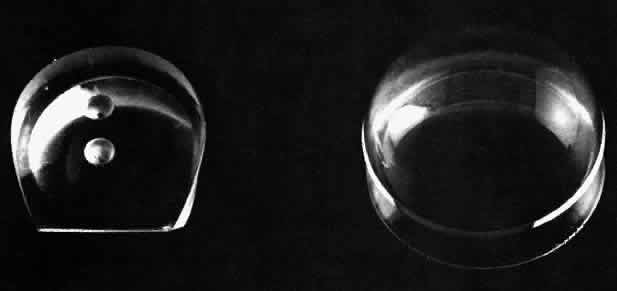

The initial therapeutic use of gonioscopy lenses was in conjunction with the performance of goniotomy operations. Although the basic technique had been described much earlier, Barkan popularized the use of this technique and obtained the excellent results that he did because he was able to see the angle structures accurately and incise them very superficially with his knife. This technique demanded a lens that left space over pan of the cornea for entry with the goniotomy knife yet provided a view of a significant portion of the angle so that at least 3 dock hours could be treated. Barkan solved this problem by designing a sort of truncated, partial Koeppe lens that included two small dimples on its surface, which could be used for stabilizing or manipulating the lens (Fig. 10). Worst designed a somewhat different lens that was actually sutured to the globe for stabilization but included a small aperture in the lens to allow for introduction of the goniotomy knife (Fig. 11).

Fig 10. A Barkan goniotomy lens (left) next to a Koeppe-type direct gonioscopy lens.